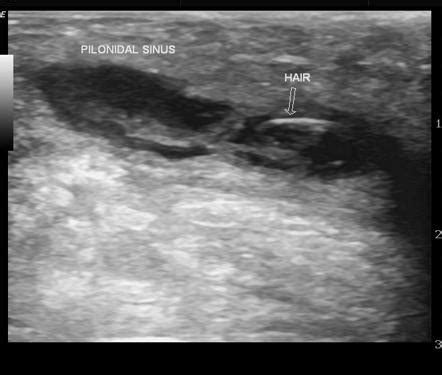

Ultrasound: The Go-To Imaging Modality

When it comes to imaging a pilonidal abscess , ultrasound is often the first tool in the radiologist’s toolkit, and for good reason, guys. It’s readily available, relatively inexpensive, and provides excellent real-time visualization of soft tissues, making it fantastic for detecting fluid collections like those pesky abscesses. The way ultrasound works is by bouncing sound waves off your body’s tissues and then interpreting the echoes to create an image. For a pilonidal abscess, the sonographer will use a transducer, which is like a wand, and apply a gel to the skin over the affected area. This gel helps to get good contact and transmit the sound waves effectively. As they move the transducer around, they’ll be looking for specific signs. The abscess itself typically appears as a well-defined, anechoic or hypoechoic area – basically, a dark or grayish area on the ultrasound screen, indicating a fluid-filled space. You might also see thickened walls around this collection, which signifies the body’s inflammatory response. The beauty of ultrasound is its ability to differentiate between solid and cystic structures. So, it can confirm that what they’re seeing is indeed an abscess filled with pus, rather than a solid tumor or other mass. Furthermore, ultrasound can help assess the size of the abscess, its depth, and its relationship to nearby structures, like muscles or blood vessels. This information is crucial for surgical planning, helping the surgeon decide on the best approach for drainage or excision. In some cases, ultrasound can even be used during the drainage procedure, guiding the needle precisely into the abscess cavity to ensure complete evacuation of the pus. This real-time guidance is a huge advantage. While ultrasound is great, it’s important to remember that it’s highly dependent on the skill of the sonographer and can sometimes be limited in obese patients or if there’s a lot of gas in the bowel overlying the area. But generally speaking, for initial evaluation and confirmation of a pilonidal abscess, ultrasound is a true workhorse in the radiology department.

So, when a radiologist looks at the images – be it an ultrasound, CT, or MRI – of a suspected pilonidal abscess , what are they specifically searching for? Guys, it’s like a detective hunt for clues! The primary goal is to confirm the presence of an abscess, which is essentially a collection of pus. On imaging, this typically appears as a well-defined area of fluid. In ultrasound , it’s often seen as a dark (anechoic) or mixed-echogenicity area with potentially thickened walls. On CT and MRI , these collections usually show up as areas of low signal intensity on certain sequences, often with a rim that enhances brightly after contrast administration, indicating inflammation. Another key thing radiologists look for is the size and extent of the abscess. Is it a small, localized collection, or is it a large, sprawling one? This information directly influences how it will be managed. They also assess its location relative to important anatomical structures. Is it superficial, or is it deep? Is it near the midline, or off to one side? This helps surgeons plan their approach. A critical finding, especially in recurrent cases, is the presence of sinus tracts . These are abnormal tunnels that can extend from the abscess or the original pit in the skin. Radiologists meticulously look for these tracts, as their identification is crucial for successful surgical treatment. They might appear as thin, linear areas of abnormal enhancement after contrast. The radiologist will describe the course, length, and any branching of these tracts. Finally, they are on the lookout for associated findings that might indicate a more complex situation. This could include surrounding inflammation of the skin and subcutaneous tissues (cellulitis), evidence of bone infection (osteomyelitis, though rare), or other rare complications. Interpreting these findings requires a deep understanding of both anatomy and pathology, making the radiology report a vital piece of the puzzle for the treating physician managing the pilonidal abscess . The radiologist’s detailed description helps paint a clear picture, guiding the clinician towards the most appropriate and effective treatment strategy for the patient.